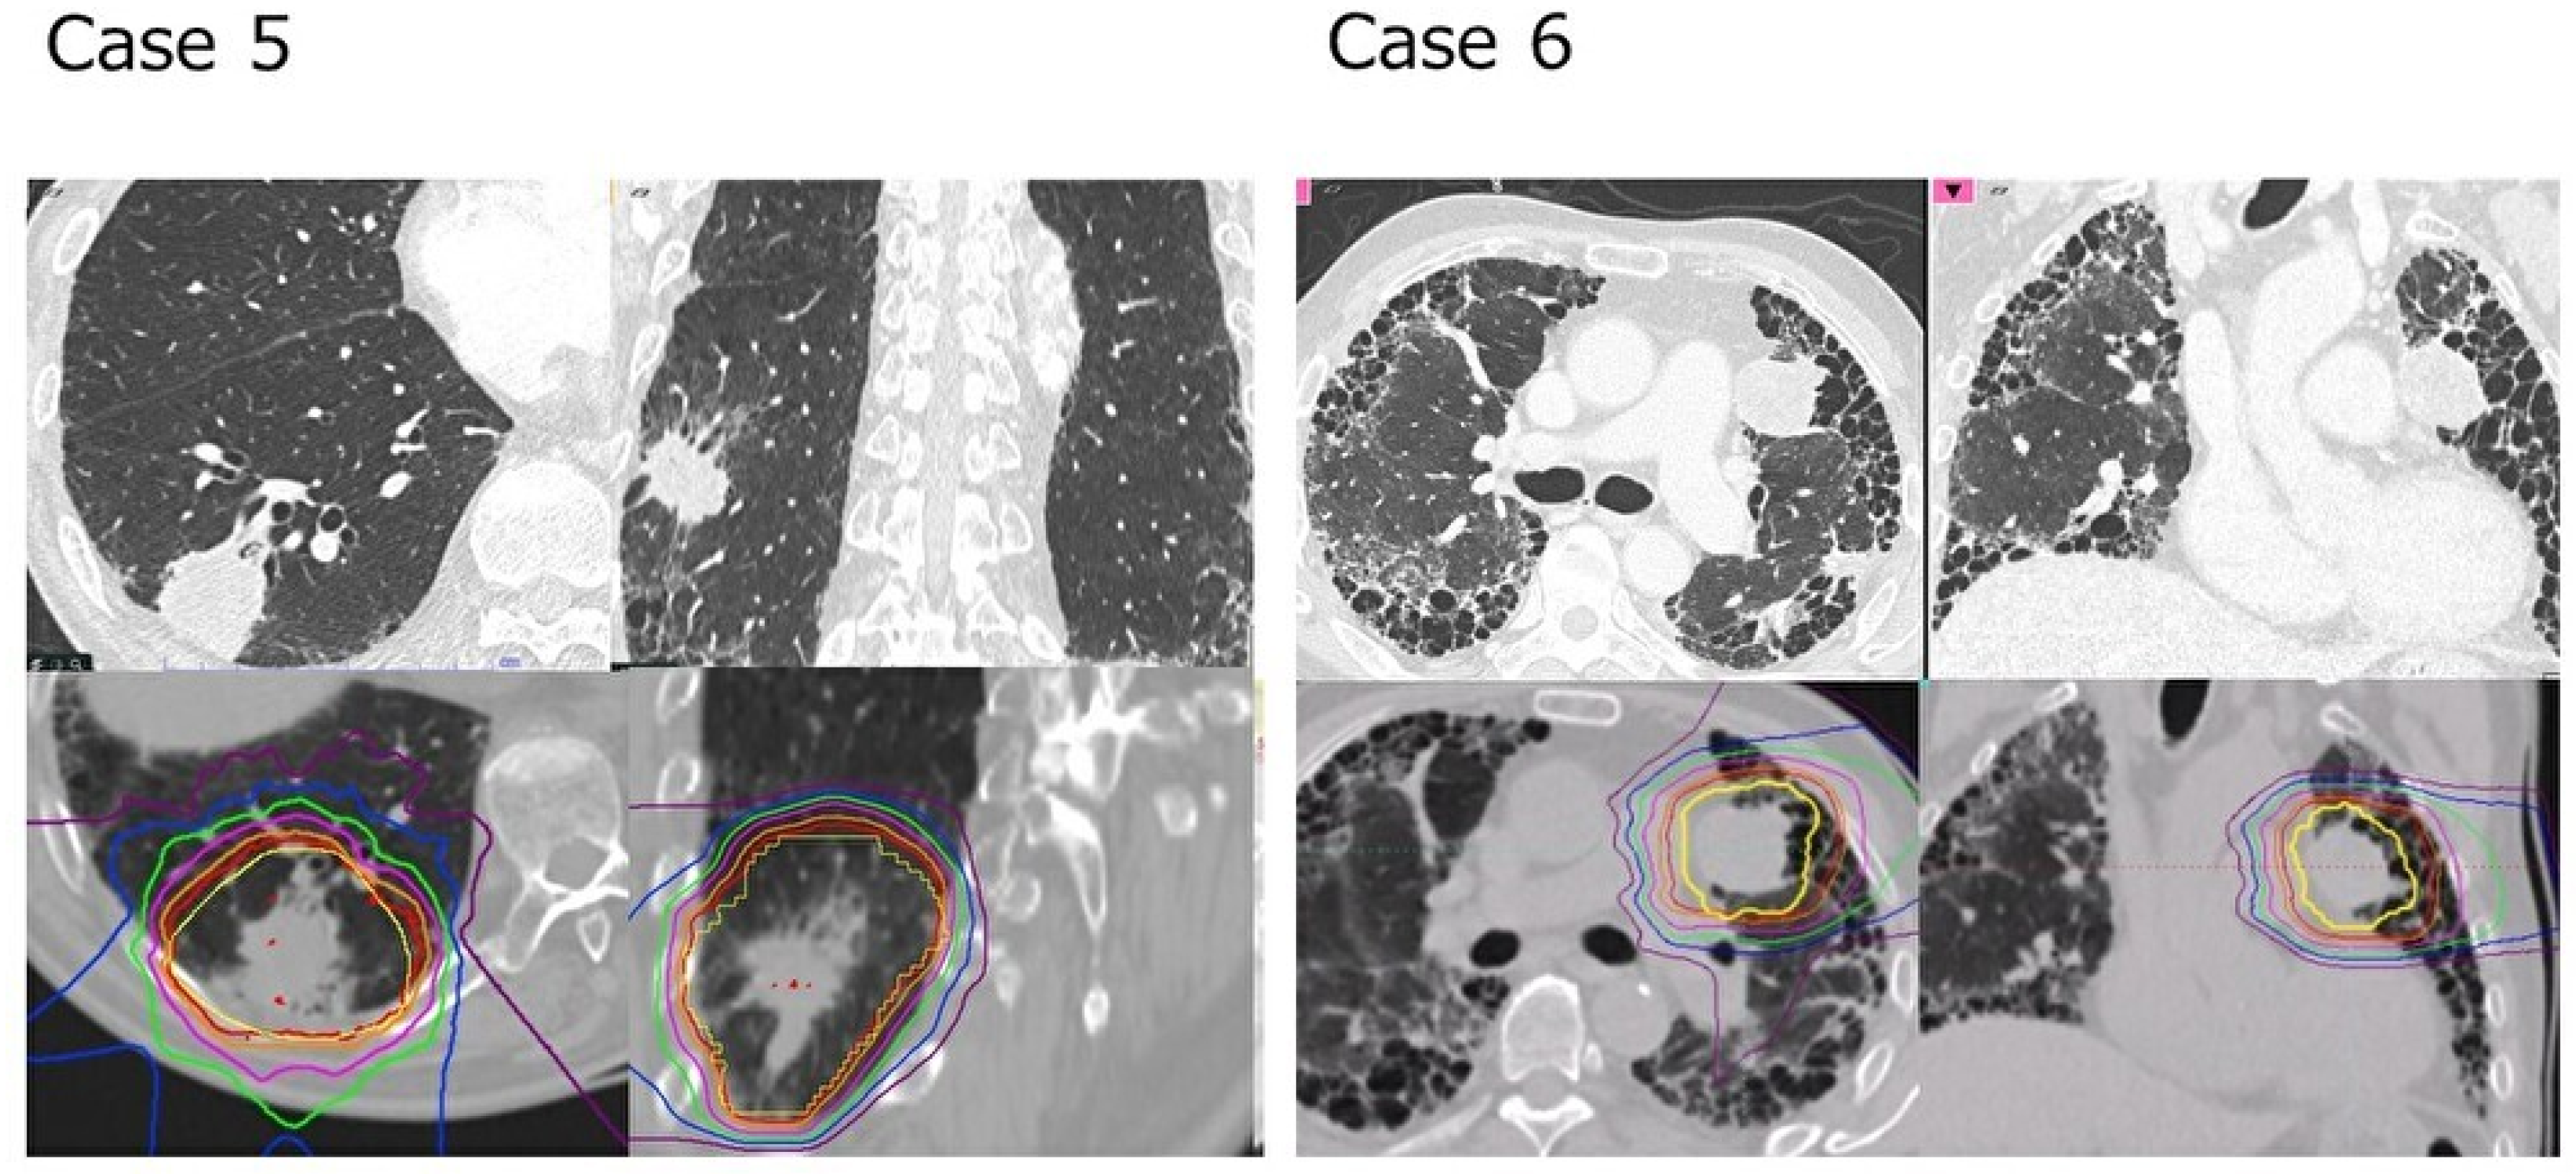

AEs were discussed in 49 of the 50 patients, excluding one patient who died of the primary disease within 2 months. Of the 49 patients in the present study, RP of grades 2, 3, and 5 were encountered in two patients (4.1%) each, totaling six patients (13%) (Table 4). Figure 2 shows the pretreatment thin-slice CT and dose distribution of the two patients with grade 5 pneumonia. The median duration of onset was 3 months (range, 1–6 months). Two patients who developed grade 5 RP presented with symptoms within 1 month of starting CIRT, indicating that early onset should be carefully monitored as a sign of severe pneumonia. Both patients died of respiratory failure 5 months after treatment and multiple steroid pulse therapies. No tumor recurrence was observed in either of the patients. Five of 32 patients (15.6%) with a UIP pattern developed grade 2 or higher RP, whereas only one (5.9%) of 17 patients without a UIP pattern. Statistical evaluation failed to show any significant correlation between RP and any of the patient backgrounds, serum markers, respiratory function, or lung irradiation doses previously reported to be associated with RP. When patients were classified using the rGAP model, RP tended to be present in patients with a higher rGAP stage (Table 5).

Figure 2.

Pretreatment CT images and CIRT dose distribution of two patients with grade 5 radiation pneumonitis (cases 5 and 6 in Table 4) are shown. Both patients had a UIP pattern and clinical stage 1B (tumor diameter 39 and 31 mm, respectively). Case 5 had a mild IP, rGAP-stage 1, but a relatively higher lung dose (lungV5/V20 of 19.18%/8.07%, respectively). Case 6, on the other hand, was a patient with severe IP in rGAP-stage 3 and on HOT but with a lower lung dose (lungV5/V20 8.64%/5.48%, respectively). The red, orange, magenta, green, blue, and purple lines show dose levels of 95, 90, 70, 50, 30, and 10%, respectively; CTV is drawn in yellow.